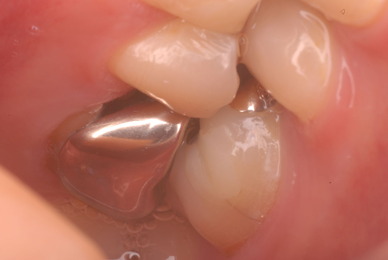

色々不満な入れ歯です。

発音や見える金属が気になるようです。

ご自分でやられても歯茎から血が出ないと話をされていましたが、私がブラシを当てると悲惨な状態であることがわかりました。